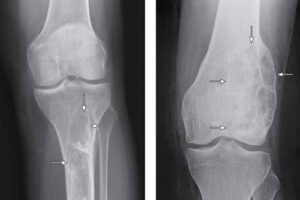

- Рентген. Рентгеновские лучи обеспечивают изображения плотных структур, таких как кость. Рентгеновский снимок выявляет крапчатый вид во внутренней части кости. Также может быть эрозия твердой внешней части кости, некальцинированные массы мягких тканей или расширение диафиза (длинной части кости) из-за роста опухоли.